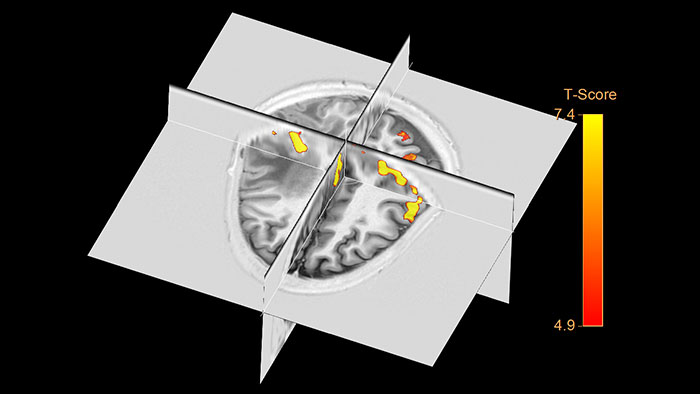

Brain activation analysis

Helps to identify and visualize functional regions of the brain, relying on local metabolic and hemodynamic changes that occur in activated brain areas.